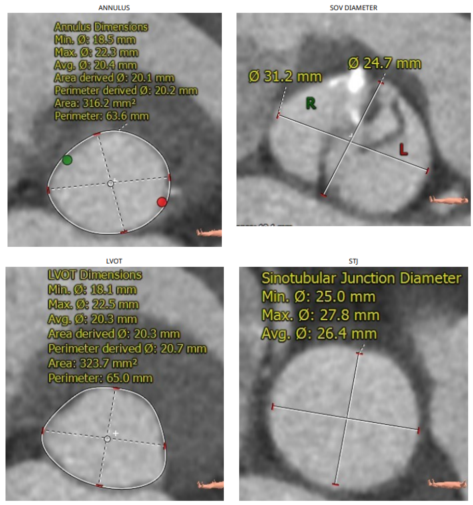

患者是一名70岁女性,门诊心脏超声提示患者有退行性心脏瓣膜病变、主动脉瓣重度狭窄、二尖瓣轻度反流、三尖瓣轻度反流、肺动脉高压、左室舒张功能减退、升主动脉增宽且既往有高血压病史。

第4例患者术前CT